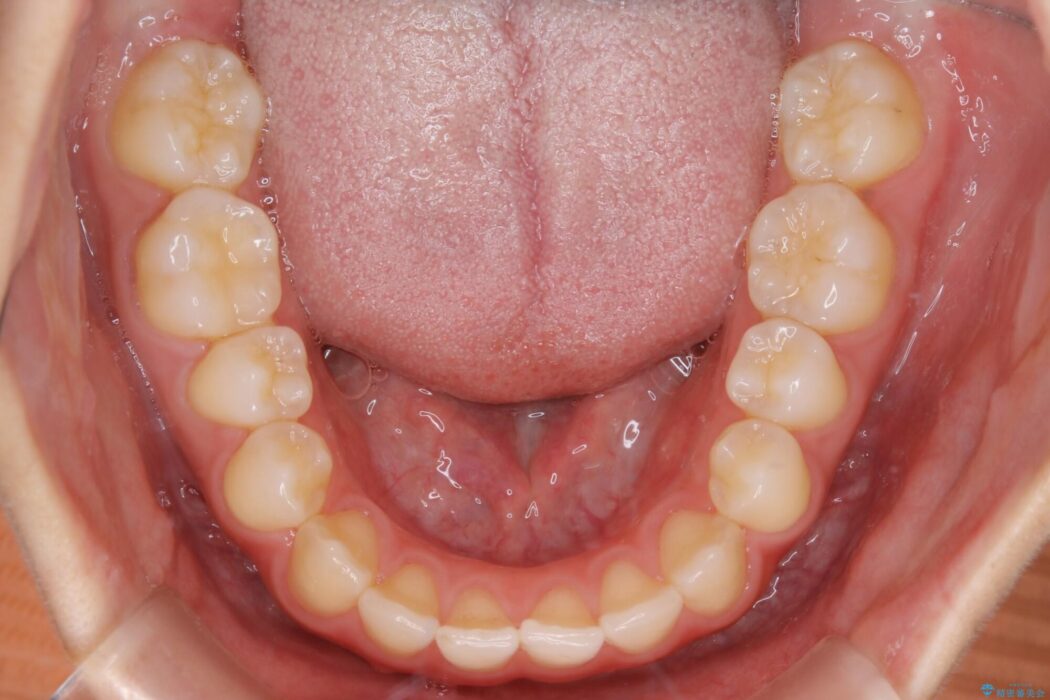

検査したところ叢生度合いから抜歯をせずとも治療が可能と判断しましたので、インビザラインでの非抜歯矯正を行う方針としました。